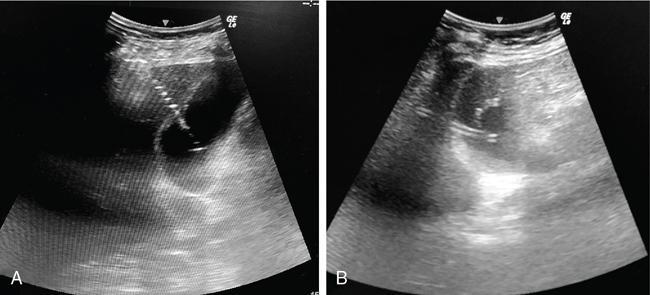

PC is a minimally invasive procedure which involves placement of a drainage catheter into the gallbladder, usually under USG guidance. It is most commonly performed to decompress an inflamed gallbladder in cases where surgery is not possible due to associated comorbidities. The indications of PC can be divided into those that require access into the gallbladder and those that require biliary tract access. The common indication for PC is acute cholecystitis due to calculus obstruction of the gallbladder neck or cystic duct in poor surgical candidates or patients with severe cholangitis. The definitive treatment for acute cholecystitis is laparoscopic cholecystectomy. Another application is for stone removal or percutaneous cholecystolithotomy through this route. PC can also be used for biliary drainage or decompression in cases where the biliary system is not dilated, particularly when the obstruction is below the level of cystic duct–bile duct junction. PC is also used for biliary diversion in the setting of a bile leak or duodenal fistula in inflammatory or traumatic conditions, thereby reducing the risk of biliary peritonitis. For intraluminal procedures, PC can act as an access portal in case the peripheral bile ducts are inaccessible. The prerequisite for PC is that the gallbladder must be distended for allowing its puncture. Contraindications to PC include unavoidable interposed bowel segment between the gallbladder and the puncture site and biliary peritonitis. Presence of coagulation disorders is a relative contraindication. This includes review of the patient’s clinical status and imaging. Screening USG should be done to evaluate the gallbladder – whether distended or not, the site of obstruction, and to decide the approach. PC is usually performed under real-time USG guidance. CT or fluoroscopic guidance is rarely used due to limited availability, exposure to ionizing radiation and higher cost. In sick patients, the procedure might need to be performed at the bedside, making USG a suitable modality. Like other invasive procedures, the blood parameters need to be evaluated (PT/INR, platelet count, renal function tests). An informed consent should be obtained. Intravenous access should be established. Patients who are candidates for cholecystostomy are usually sick and are usually on antibiotic treatment. In case where it is not so and there is clinical evidence of infection, third-generation cephalosporins and macrolides for covering anaerobic bacteria may be administered. This procedure is mostly done under USG guidance as this technique is readily available for bedside and emergency procedures and more cost-effective. It can also be performed under CT or fluoroscopy guidance. The procedure is done under local anaesthesia. The patient lies supine or in the left lateral position and the area is cleaned and draped. Based on the position of the gallbladder, a preferable access route is chosen, either transhepatic or transperitoneal. The second decision is about the puncture technique, which may be modified Seldinger or trocar. An 8F catheter is usually placed to allow drainage of bile. If the bile is thick and infected, a 10F or 12F catheter may be necessary. Locking pigtail catheters are useful in reducing the incidence of catheter dislodgement. The two USG-guided approaches used for PC are transhepatic and transperitoneal, of which the former is usually preferred. In the transhepatic approach (Fig. 9.24.14), the gallbladder is punctured through the liver parenchyma, generally the bare area. The traversed liver parenchyma provides better support for the catheter and helps in reducing the incidence of bile leak into the peritoneal cavity and thus biliary peritonitis. However, since liver is a vascular organ, there is an increased risk of bleeding due to the puncture of the liver. Thus, this approach should be cautiously used in patients with liver dysfunction and coagulopathies.